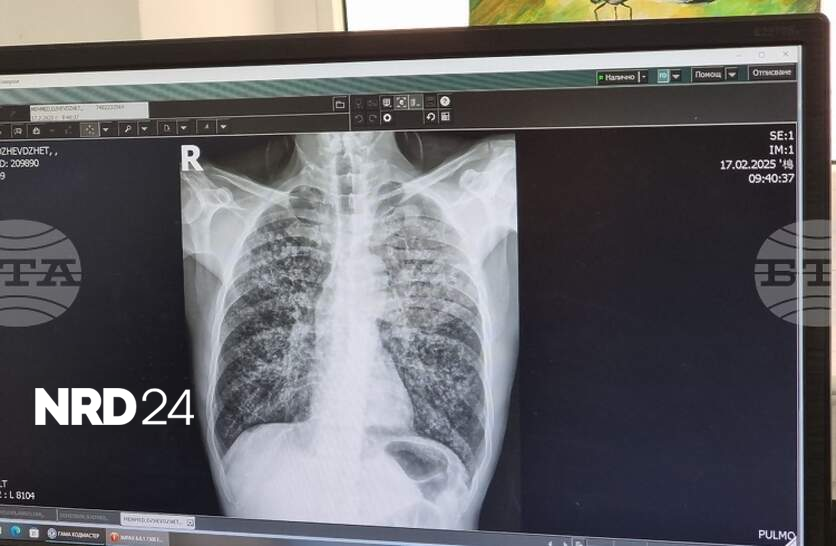

Ранна и бърза диагностика, скрининг сред уязвими групи, навременно лечение, обучения на медици, повишена осведоменост сред населението се предвиждат в проекта на Национална програма за превенция на туберкулозата в Република България 2026-2030 г. Проектът е публикуван на сайта на Министерството на здравеопазването за едномесечно обществено обсъждане. Във финансовия план към проекта на програмата са предвидени 4 440 100 млн. евро, които ще бъдат осигурени от бюджета на МЗ. В България, след 1998 г., се наблюдава трайна тенденция на намаляване на заболеваемостта от туберкулоза - от 49,9 заболели на 100 000 население през 1998 г. до 13,7 заболели на 100 000 през 2024 г. Данните на Световната здравна организация през 2024 г. показват, че приблизително 10,7 млн. души в света са диагностицирани с туберкулоза, от които 5,8 млн. са мъже, 3,7 млн. - жени и 1,2 млн. - деца. Туберкулозата е тежко инфекциозно заболяване, което засяга най-често белите дробове, но също така и други органи на човешкото тяло, като се смята, че около една четвърт от хората в света са носители на микробактерии, причиняващи туберкулоза (латентна туберкулоза). Тези хора са асимптоматични и не са заразни за околните, но средно около 10% от тях развиват активна туберкулоза. Симптомите на белодробната туберкулоза са кашлица с храчки (понякога с кръв), болка в гърдите, задух и общо усещане за слабост. Извънбелодробната туберкулоза може да засегне всяка част на тялото, като най-честата локализация са ставите и костите. Основните рискови фактори за развитие на туберкулоза са: употребата на алкохол, тютюнопушене, имуносупресия и недохранване. Риск от развитие на туберкулоза има и за хора, засегнати от ХИВ, от диабет, рак или приемащи имуносупресивни лекарства заради химиотерапия, трансплантация, ревматоиден артрит, псориазис или болест на Крон и др. В риск могат да бъдат деца, възрастни хора, лица, идващи от страни с висока честота на заболяването или живеещи в пренаселени пространства, при лоши битови условия, употребяващи с наркотици. Огромните щети, причинени от заболяването в личен и обществен план, както и значителните разходи за изграждане и функциониране на система за откриване на случаите, диагностика и лечение, налагат необходимостта от предприемане на действия за ограничаване на разпространението му. МЗ провежда дългогодишна политика по превенция на туберкулозата чрез приемане и изпълнение на национални програми в четири програмни периода - 2007-2011 г., 2012-2015 г., 2017-2020 г. и 2021-2025 г. Основните цели на програмите са намаляване на броя на заболелите и на починалите от туберкулоза, което е в съответствие с Целите за устойчиво развитие на ООН, Стратегията на СЗО за край на туберкулозата до 2035 г. и Плана за действие на Европейския регион на СЗО за намаляване на туберкулозата до 2030 г.